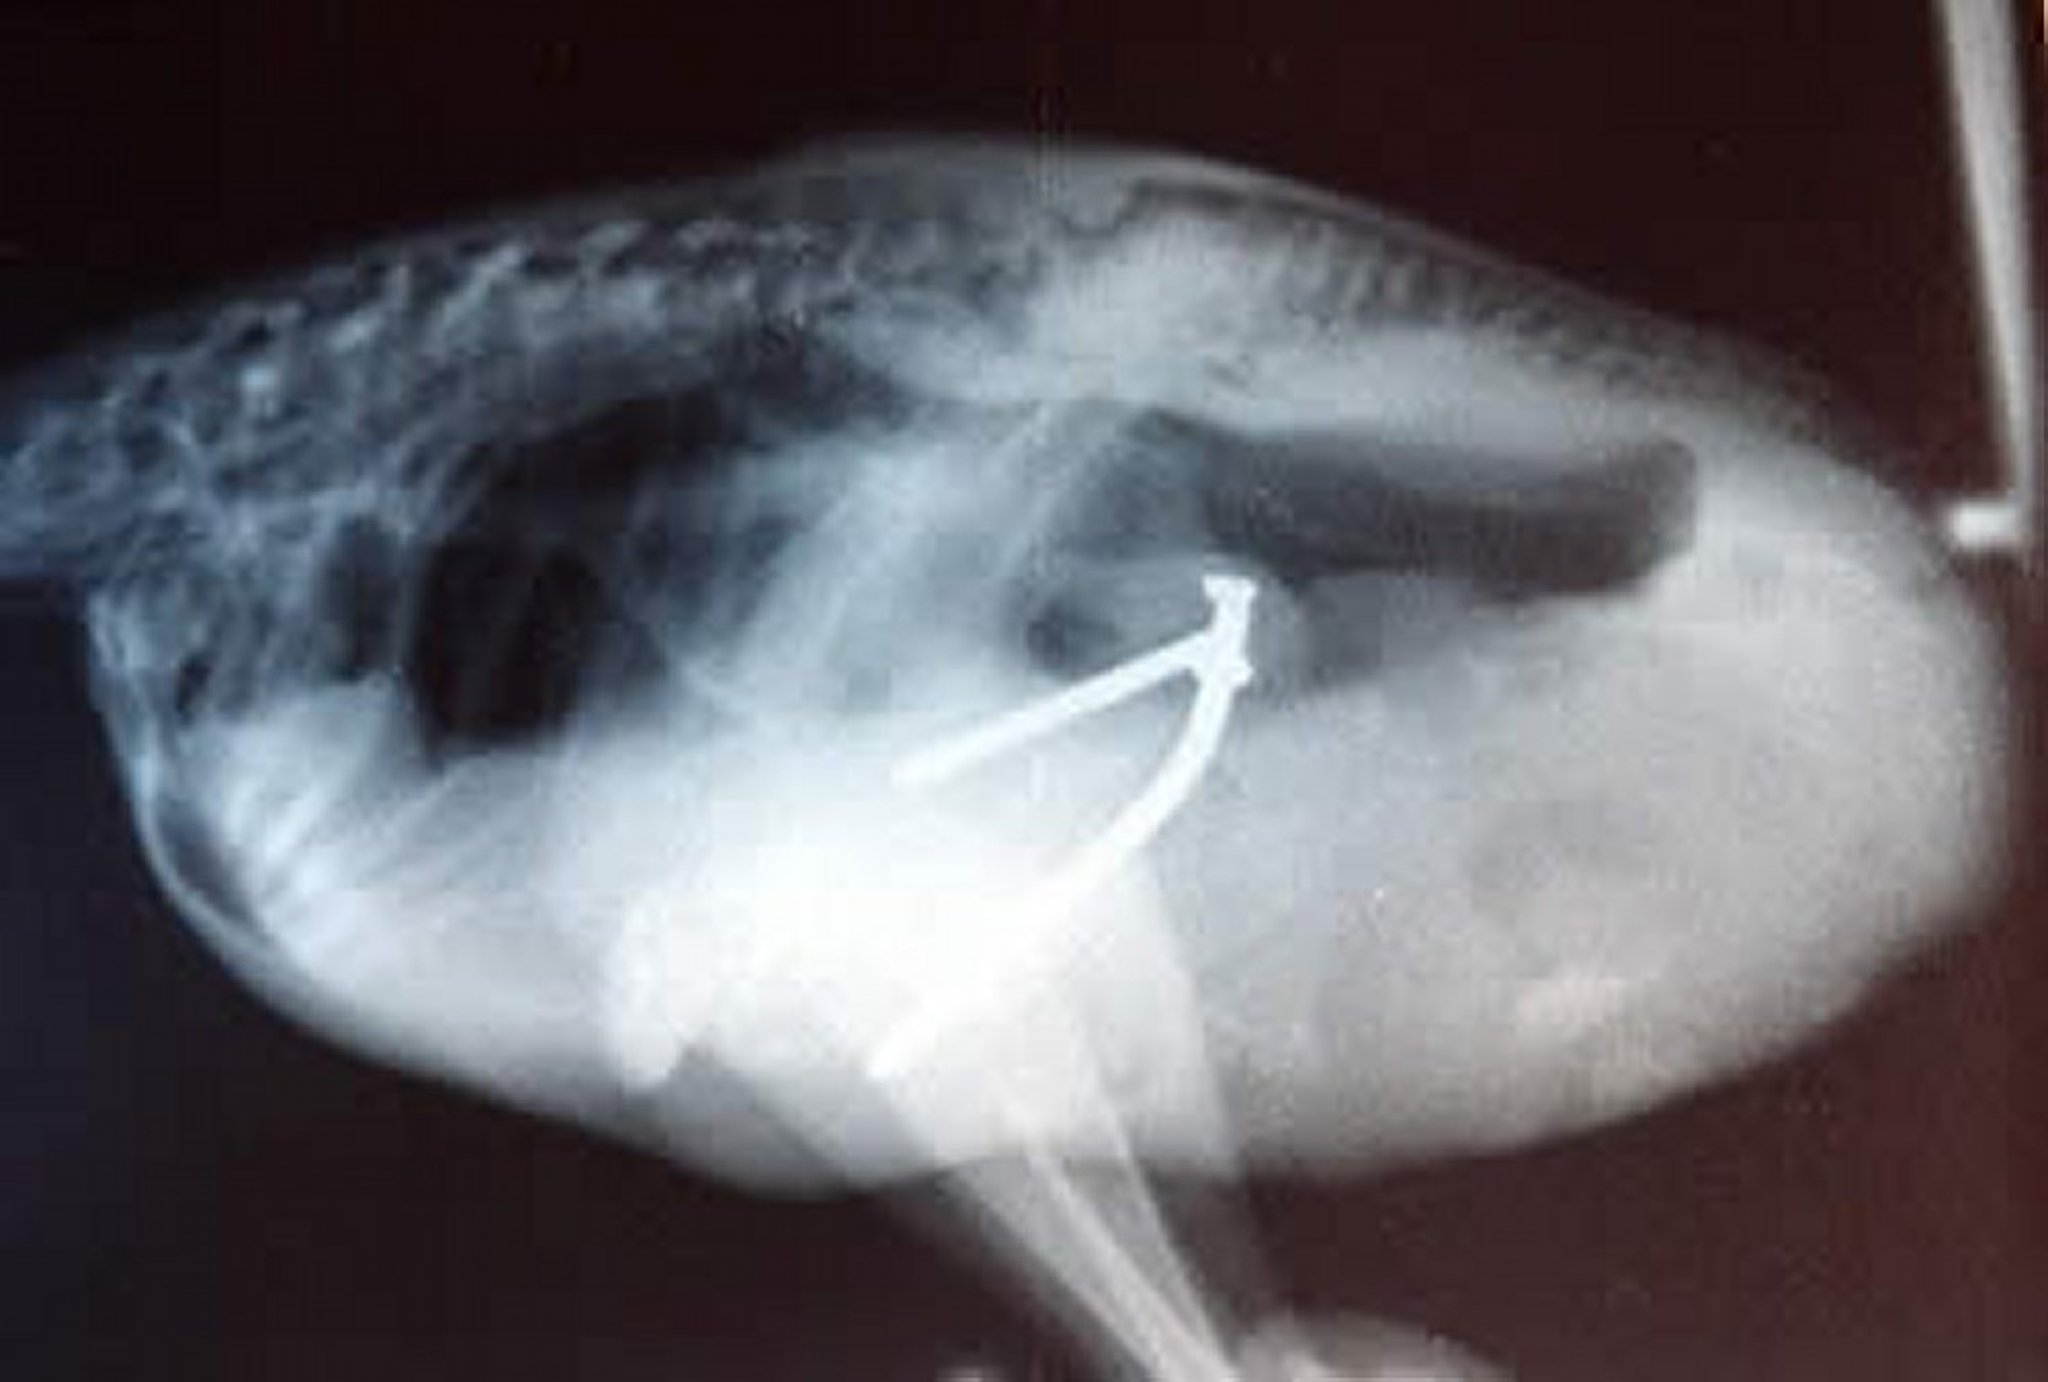

Radiograph (lateral projection) revealing metallic foreign bodies in a 6-week-old ostrich chick.

Courtesy of Dr. Karen Hicks-Alldredge.

Impaction of the proventriculus and ingestion of foreign bodies are management-related problems. Chicks are at high risk of impaction for the first 2 weeks after movement to a new environment, with or without a change in substrate or diet. Proventricular impactions are also diagnosed as a sequela of diseases involving ileus of the GI tract. Impactions with sand and concentrated feed can be managed medically with psyllium laxatives and supportive care. Impactions with forages or ingestions of foreign material (eg, hardware, rocks, jewelry) require proventriculotomy surgery for removal and subsequent resolution of the problem.